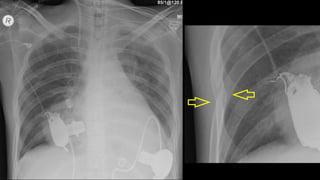

“APICAL CAPPING”

HEMATOMA MEDIASTINAL

> 8 cm

Traqueia desviada

Mediastino

alargado